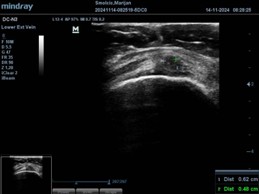

A detailed clinical examination of the rotator cuff was strongly positive on all provocation tests, suggesting significant tendon involvement. A diagnostic shoulder ultrasound then revealed a major tendon rupture, visible as a black defect measuring approximately 6.5 × 5.5 mm, corresponding to a tear affecting more than half of the tendon width.

Shoulder injury treatment in Zagreb – before therapy